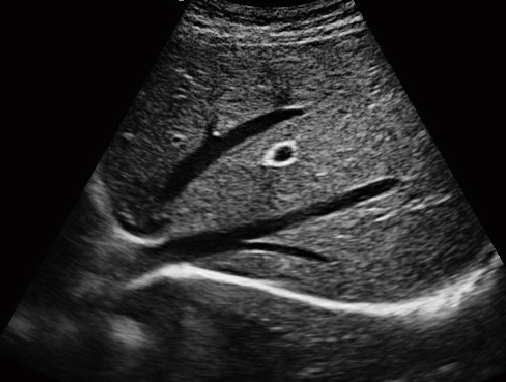

·顯示模式:B、B+B、4B、B+M、M、PW

·具有專業的動物產科軟件包,分別是狗、貓、馬、牛、羊

·適用于各種動物的臨床腹部、胸腔,心臟、肌腱、小器官、眼球、生殖系統等的檢查